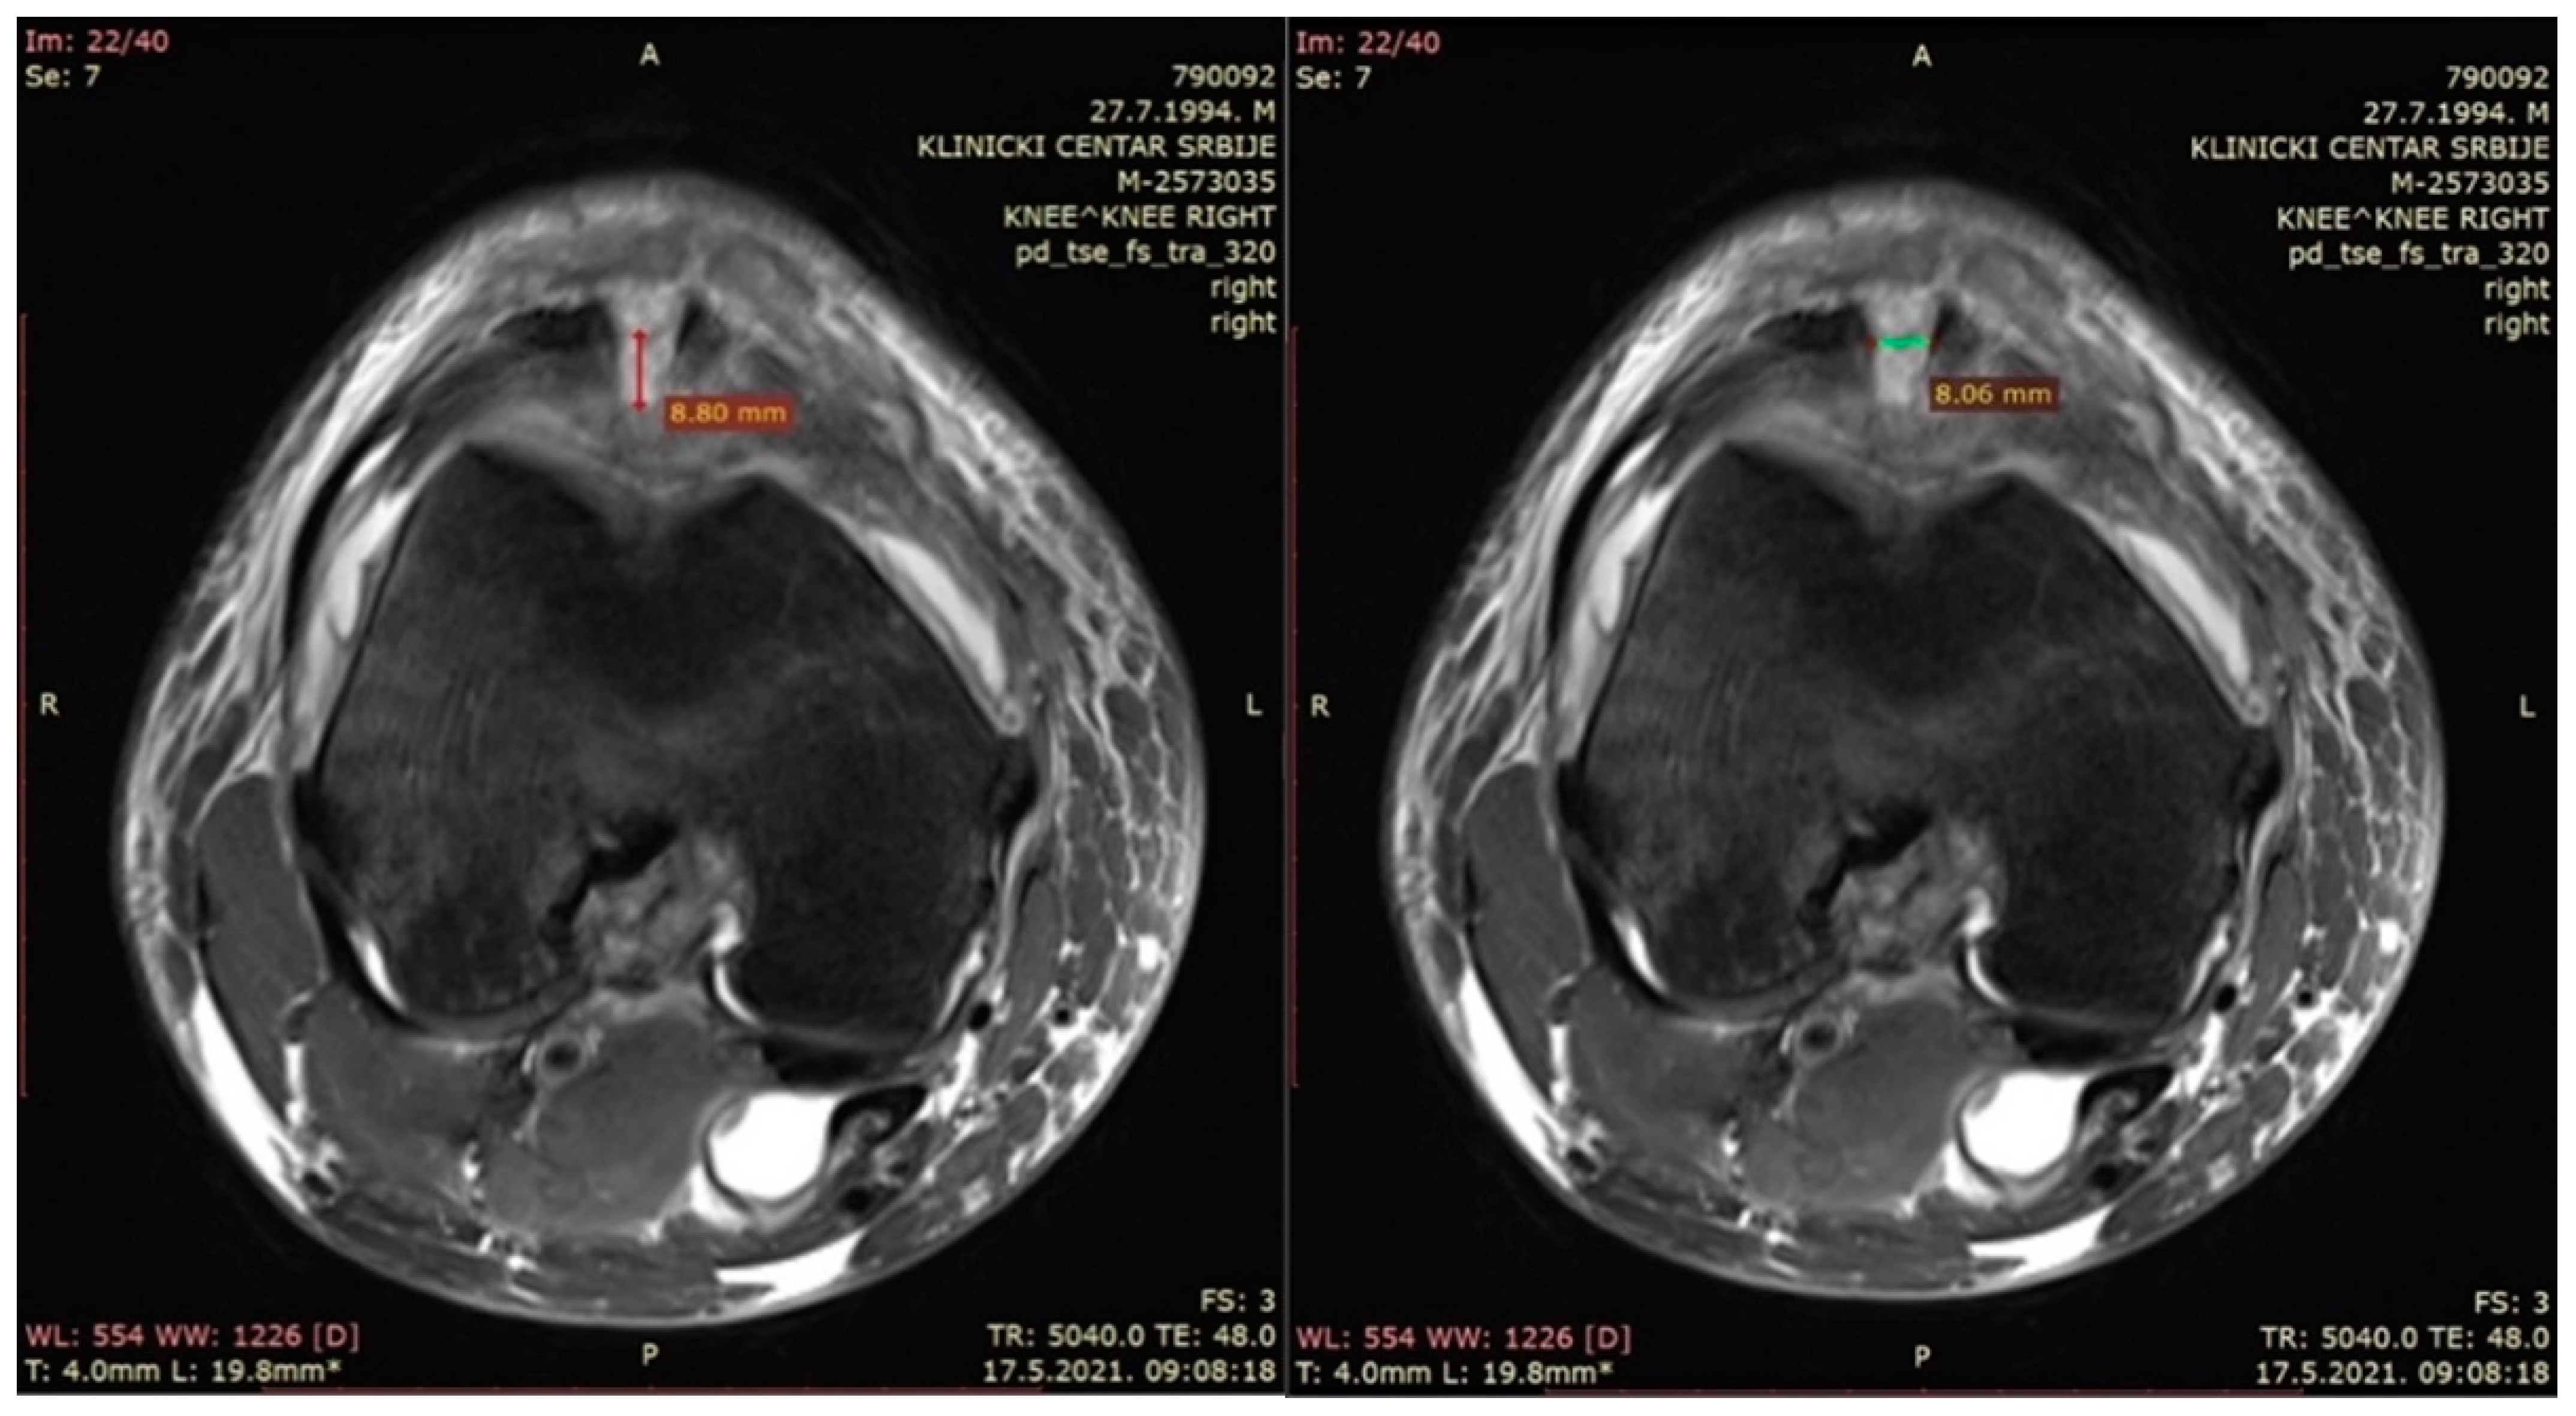

- The depth of the patellar bone defect (mm)—a variable used to assess the depth of the bone defect from the first section caudal to the top of the defect in a transverse plane in the t2_tse_sag sequence at the center of the defect, as defined using the sagittal plane (Figure 3—left).

- The width of the patellar bone defect (mm)—a variable used to assess the width of the bone defect from the first section caudal to the top of the defect in a transverse plane in the pd_tse_fs_tra sequence (Figure 3—right).